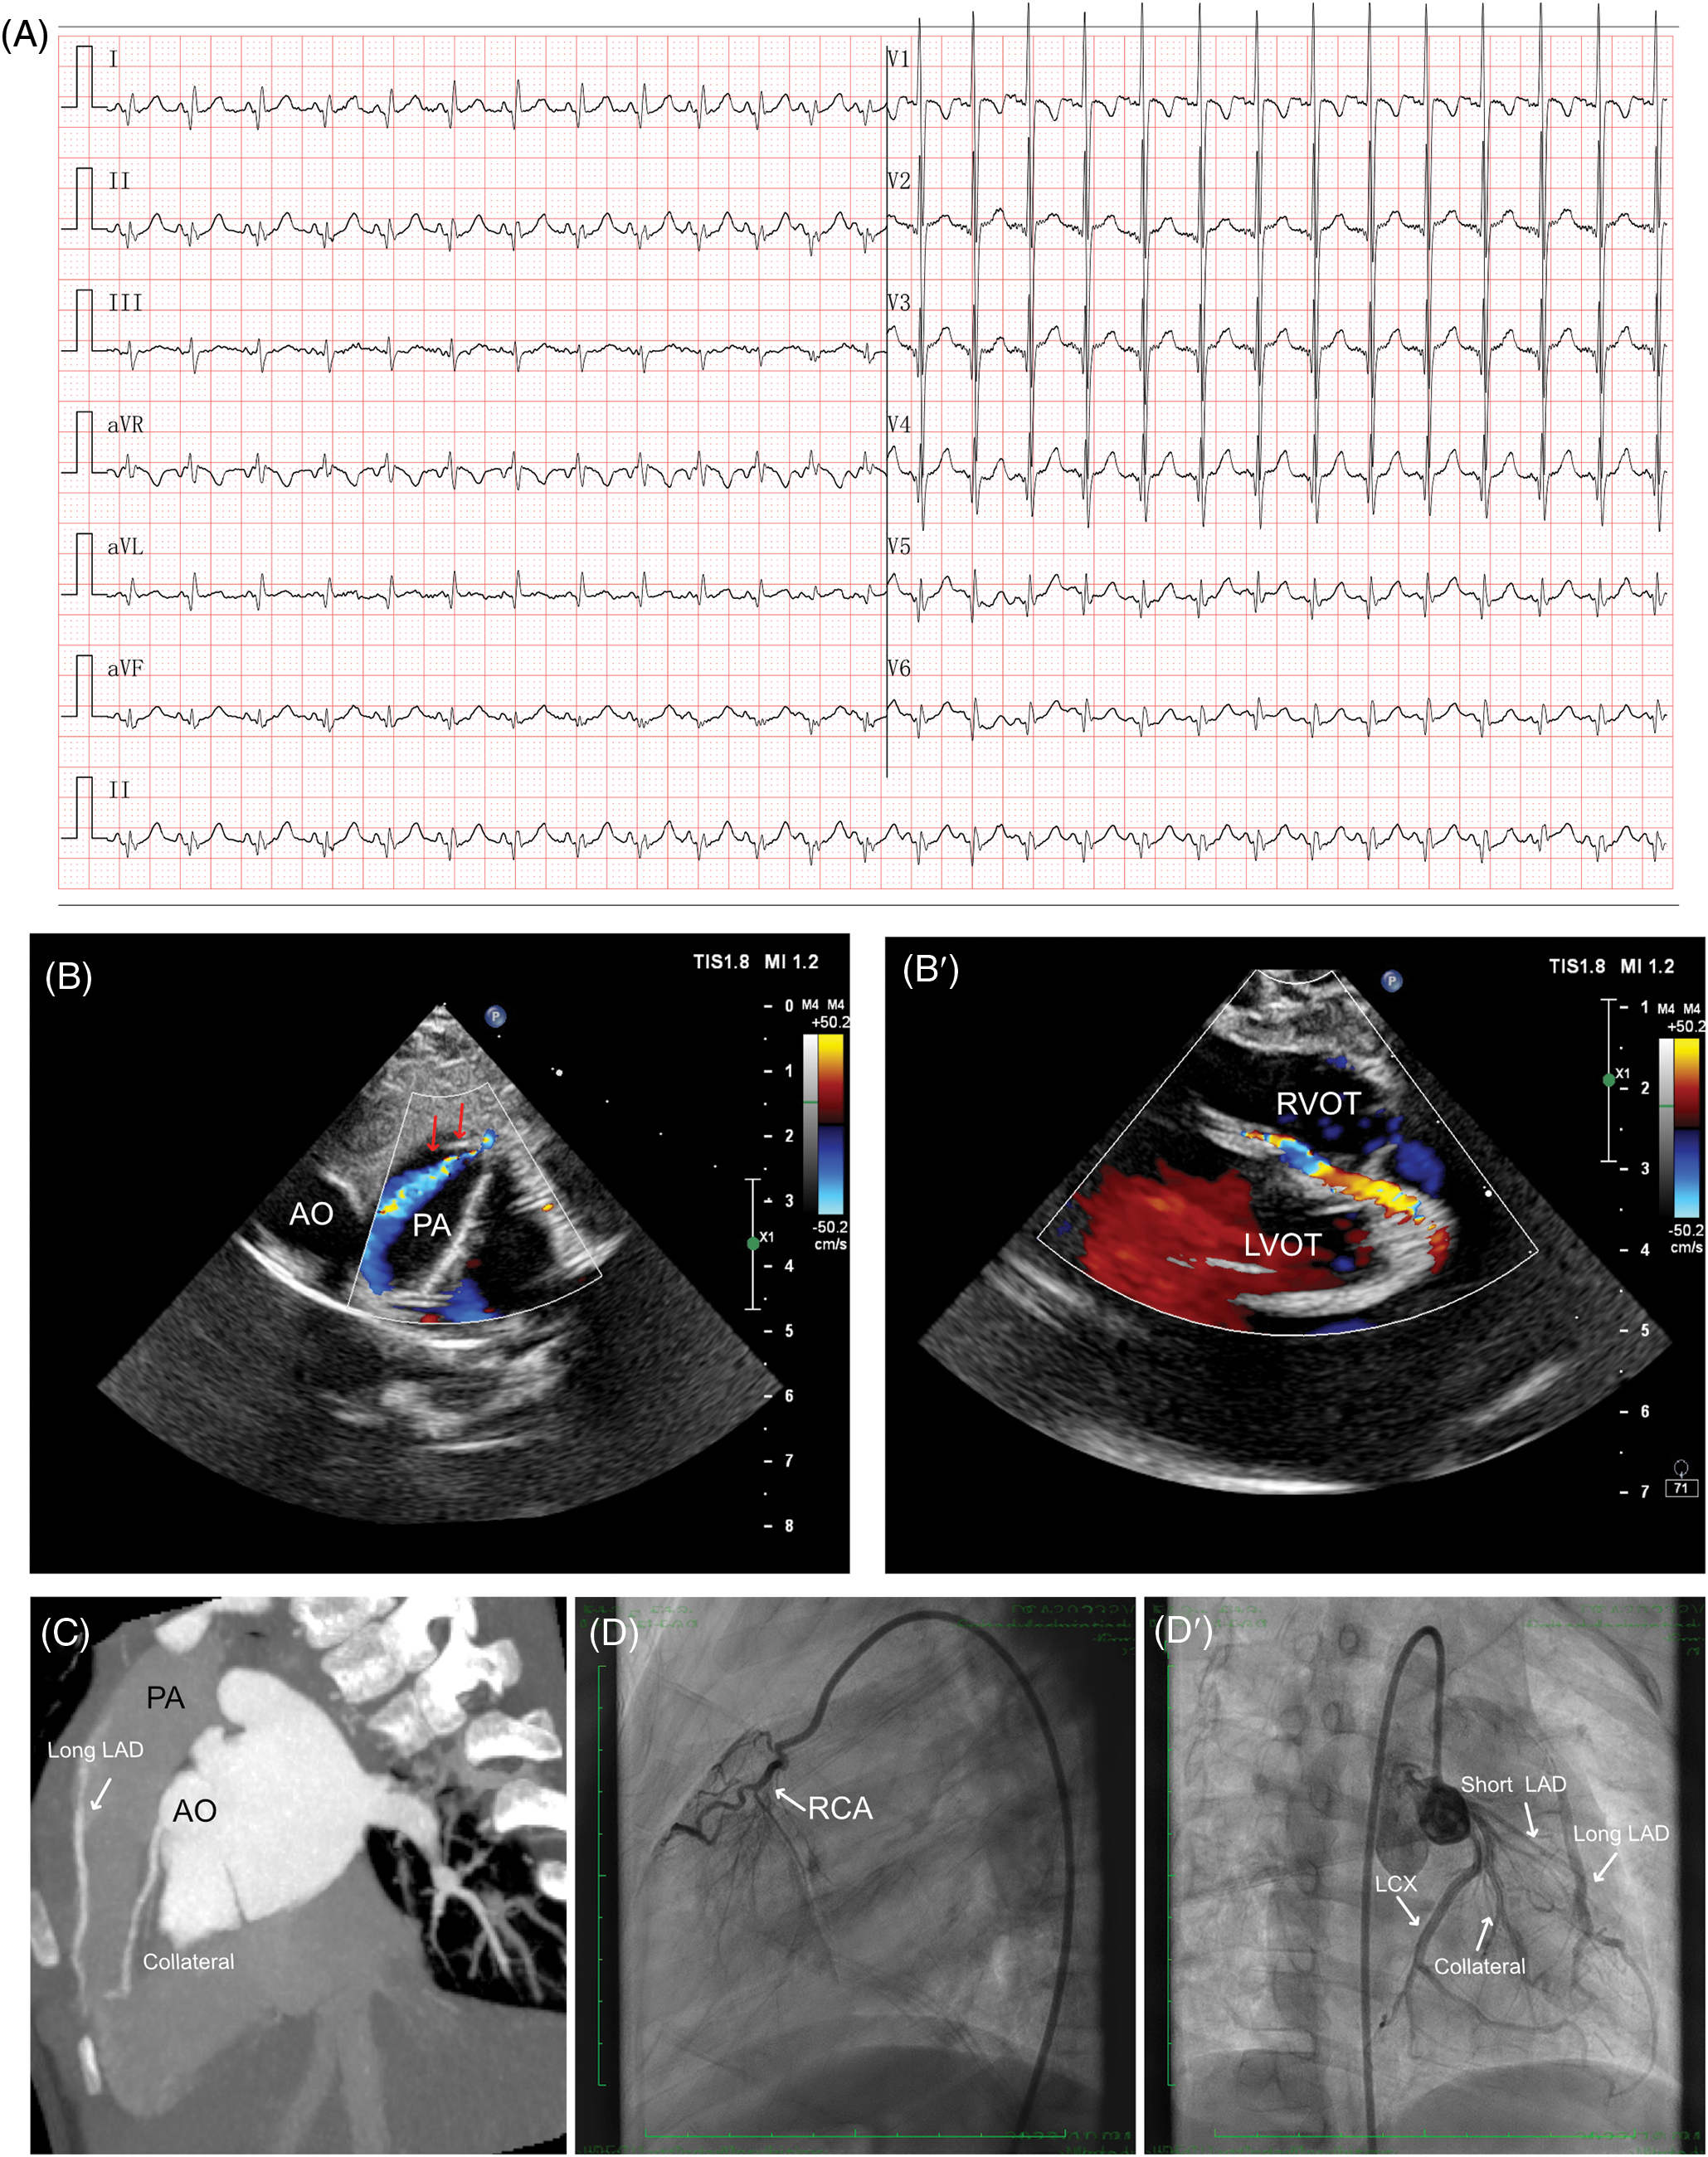

The first case was a 31-month-old female who initially presented an increased heartbeat. Then a routine electrocardiogram (ECG) was performed which demonstrated sinus tachycardia, and an abnormal q wave was observed in I and aVL leads (Fig. 1A). Although serum levels of B-type natriuretic peptide (85.00 pg/mL; n.v. < 100 pg/mL) and troponin I (0.02 µg/L, n.v. < 0.06 µg/L) were normal, the abnormal coronary circulation was suspected due to abnormal q wave had been noticed. The echocardiography demonstrated LMCA arising normally from the aorta sinus, left circumflex artery (LCX) and slender LAD originated from the LMCA, while an abnormal blood shunting flowing into PA and a dilated collateral originated from LMCA coursing to the septum. Thus, the differential diagnosis should be completed among the suspected anomalous origin of the coronary artery, small coronary artery-PA fistula, and coronary artery-right ventricle fistula (Fig. 1B,B′). Then computed tomography angiography (CTA) revealed a dominant functional LCX and a high origin of the right coronary artery (RCA) above the right coronary sinus (RCS). The LMCA originated from the left coronary sinus (LCS) and emitted a short LAD, LCX, and several collateral coronary arteries with a long margining artery coursing in the interventricular groove, originating from PA (Fig. 1C). After that, the transcatheter angiography demonstrated that the short LAD perfused a set of communicating branches to the septum myocardium, and the long LAD draining a few volumes of blood into PA. Besides, there was an extensive network of blood vessels at the apex of the heart connecting the long LAD with LCX and the abnormal collateral coronary arteries, then reversing perfused the short LAD (Fig. 1D,D′, Video S1).

Figure 1: Clinical manifestation of the case I. (A) ECG findings showed sinus tachycardia and abnormal q wave could be observed in I and aVL leads. (B, B′) Echocardiography indicated a suspected anomalous origin of the coronary artery, a small coronary artery-PA fistula (red arrows), and a dilated collateral originating from LMCA coursing to the septum. (C) CTA demonstrated a dual LAD structure, as short LAD arising from LMCA and long LAD arising from PA. (D, D′) Transcatheter angiography revealed a short LAD perfused a set of communicating branches to the septum myocardium and the long LAD which was draining a few volumes of blood into PA. CTA, cardiac computed tomography angiography; ECG, electrocardiogram; RCA, right coronary artery; LMCA, left main coronary artery; LAD, left ascending coronary artery; LCX, left circumflex artery; PA, pulmonary artery; AO, aorta; RVOT, right ventricular outflow tract; LVOT, left ventricular outflow tract